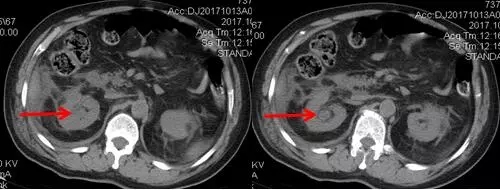

術(shù)后CT,箭頭所指為腎結(jié)石被徹底清除

三日后,曾奶奶病情逐漸穩(wěn)定,各項(xiàng)感染指標(biāo)逐漸恢復(fù)正常,復(fù)查CT顯示腎結(jié)石已經(jīng)被完全清除,現(xiàn)已康復(fù)出院。就此,困擾曾奶奶多年,反復(fù)感染差點(diǎn)致命的腎結(jié)石頑疾被徹底治愈。曾奶奶全家人對于愛康醫(yī)院泌尿外科專家高超的碎石取石手術(shù)技藝更是贊許有加,對泌尿外科團(tuán)隊(duì)的工作給予衷心感謝和高度評價。